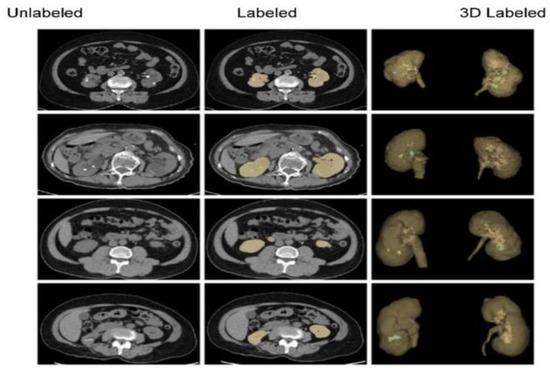

- Improved diagnostics: AI-driven image analysis tools can enhance the identification and description of pediatric kidney cancers and tumors. Radiologists can spot minor abnormalities, characterize renal masses, and estimate tumor burden more accurately using ML algorithms that have been trained on large datasets of pediatric renal images (Figure 7). AI algorithms enable the early identification of kidney cancers and tumors by methods including pattern recognition, masking, segmentation, and quantitative analysis, allowing for confident diagnosis and timely treatment [24].

- Personalized treatment planning: AI systems provide personalized therapy recommendations and perform the prognostic evaluation of patient-specific data, including clinical history, imaging results, and laboratory values. For young patients with kidney cancers, this customized strategy enables medical practitioners to maximize therapeutic efficacy, reduce treatment-related morbidity, and enhance long-term outcomes [43].

- Predictive modeling and risk stratification: AI predictive modeling enables doctors to identify children with kidney tumors who are more likely to experience treatment failure or disease progression. ML algorithms identify prognostic characteristics and biomarkers through the analysis of varied datasets. This improves treatment outcomes and survival rates for children with kidney cancers by empowering doctors to use tailored risk mitigation strategies and start treatment early [44].